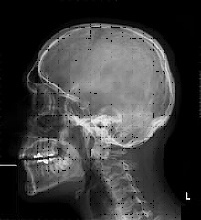

Per radiografia si intende lo studio, il più dettagliato possibile, di un segmento scheletrico o di un distretto, attraverso l'utilizzo di radiazioni elettromagnetiche di tipo x, dette anche ionizzanti, per la loro proprietà di emettere ioni. E' questo un antico, ma pur sempre valido esame di primaria importanza, quando viene utilizzato in circostanze particolari, come in un incidente, per valutare gli eventuali danni articolari o in caso di trauma cranici; in casi di emergenza rappresenta la principale fonte d' informazioni, in quanto la consultazione risulta estremamente dettagliata e chiara.

Si riprodurrà quindi una immagine del tutto simile al corpo, ma in negativo, come una vera e propria fotografia, in quanto i fotoni che non vengono assorbiti, restano impressi sulla pellicola. L'esame a raggi x, in grado di fornire immagini di strutture anatomiche, per scopi diagnostici, consiste in effetti nell'imprimere su una pellicola radiografica le diverse densità dell'organismo, la pellicola risulterà più o meno scura a seconda della struttura rilevata. Tutto ciò avviene perché, quando i raggi x attraversano la materia, producono ioni, la nitidezza dei particolari degli organi interni che appaiono diversamente opachi, è dovuta alla loro composizione ed alle proprietà più o meno di assorbimento.

Quando i raggi x attraversano un corpo, subiscono un'attenuazione di radioattività, tanto maggiore, quanto più sono elevati lo spessore ed il peso specifico del materiale attraversato, trasferendo allo stesso parte della propria energia ed è per questo motivo che appariranno diverse tonalità:

- Le ossa saranno di colore bianco,

- I tessuti molli presenteranno diverse sfumature di grigio,

- L'aria circostante sarà nera.

Nell'apparato osteo articolare è possibile rilevare:

- Fratture,

- Nella colonna vertebrale è possibile evidenziare casi di spondilolitesi, spondiloartrosi, cifosi o scoliosi.